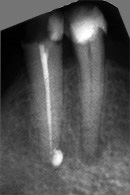

Der umfangreiche kariöse Defekt steuerte sehr bald hin auf die komplette Entfernung des Zahninnen­gewebes mit anschliessendem medikamentösen Wiederverschluss. Aufbissempfindlichkeit am Folgetermin ist immer Aufforderung zur erneuten Intensivsuche nach weiteren Kanälen, die hier einen 4. Ast zum Vorschein brachte. Nach 2 ausgelassenen Terminen

waren vorrangig Wiederherstellung von desinfizierender Einlage und provisorischer Füllung angezeigt. Eine weitere Woche später wurde in allen Kanälen das Medikament durch die endgültige Verschlussmasse ersetzt, worauf Zahn 36 mit 12-tägiger Verzögerung erneut zu rebellieren begann. Das hiess aus den hinteren Wurzeln Füllmaterial wieder raus und

Einlage erneut rein. Als es dann 4 Wochen später bei der hinteren Wur­zel aussen anzuschwellen begann und ein Medikamentenwechsel ohne Wir­kung blieb, wurden die hinteren Ka­näle abgefüllt und auch in gleicher Sitzung das überstopfte Material (Bild 1) mittels Resektion (Bild 2) von aussen entfernt.

Die ersten beiden Aufnahmen sind aus dem Jahr 1999, die 3. von 2006